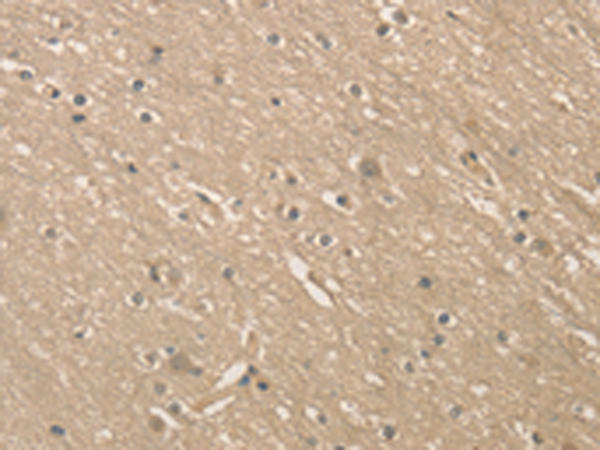

分类: 科研抗体货号: P07815别名: MMSDH; MMSADHA应用: WB,IHC反应种属: Human, Mouse, Rat